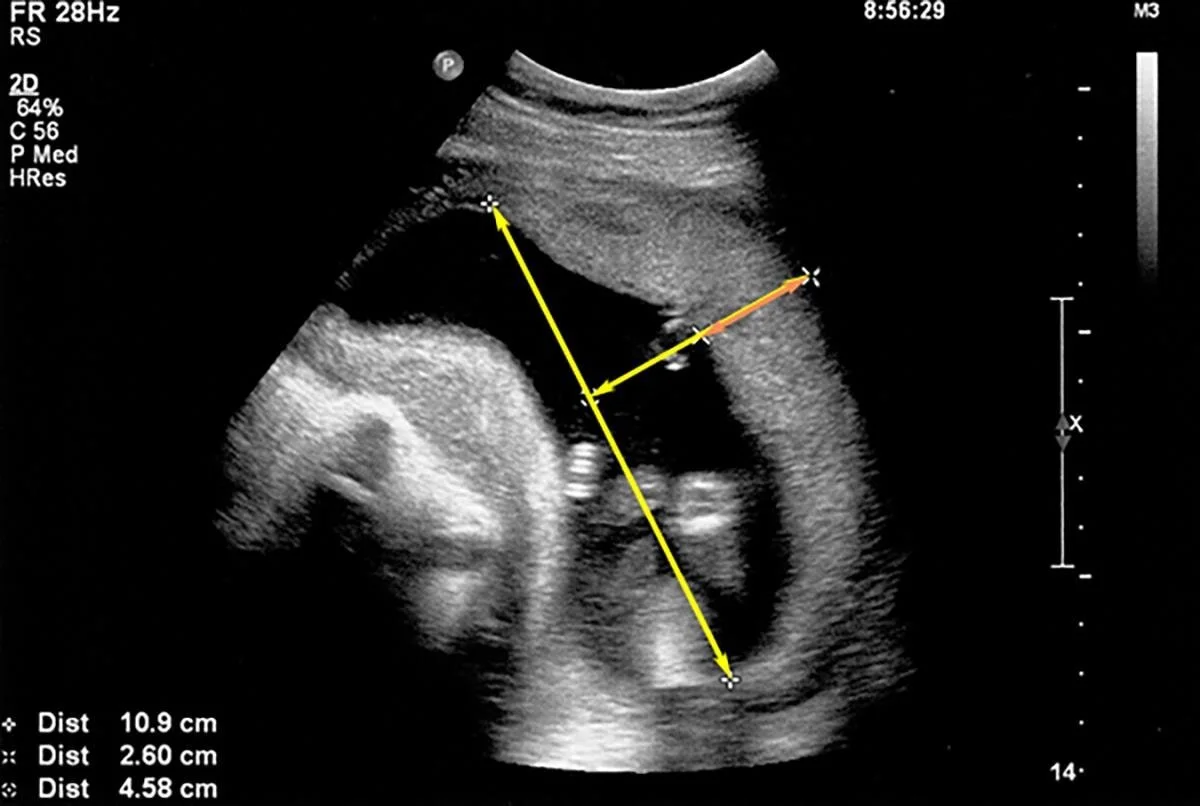

This baby’s placenta dropped below the 10th percentile by 32 weeks gestation.

Tragically, the placenta was not measured during pregnancy. Standard biophysical profiles showed a healthy pregnancy. The child was stillborn at full term.

This chart was created retroactively with ultrasounds on file. It likely would have indicated induction - and saved a life.